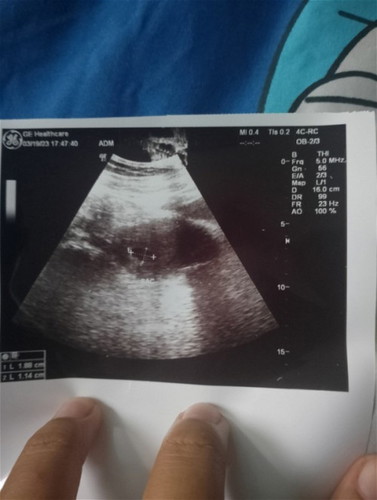

ถามหมอรอบ2/3/66หมอบอก4วิคพอวันที่19/3/66ไปฝากท้องหมอยังบอก4วิคงงมากเลยคะ